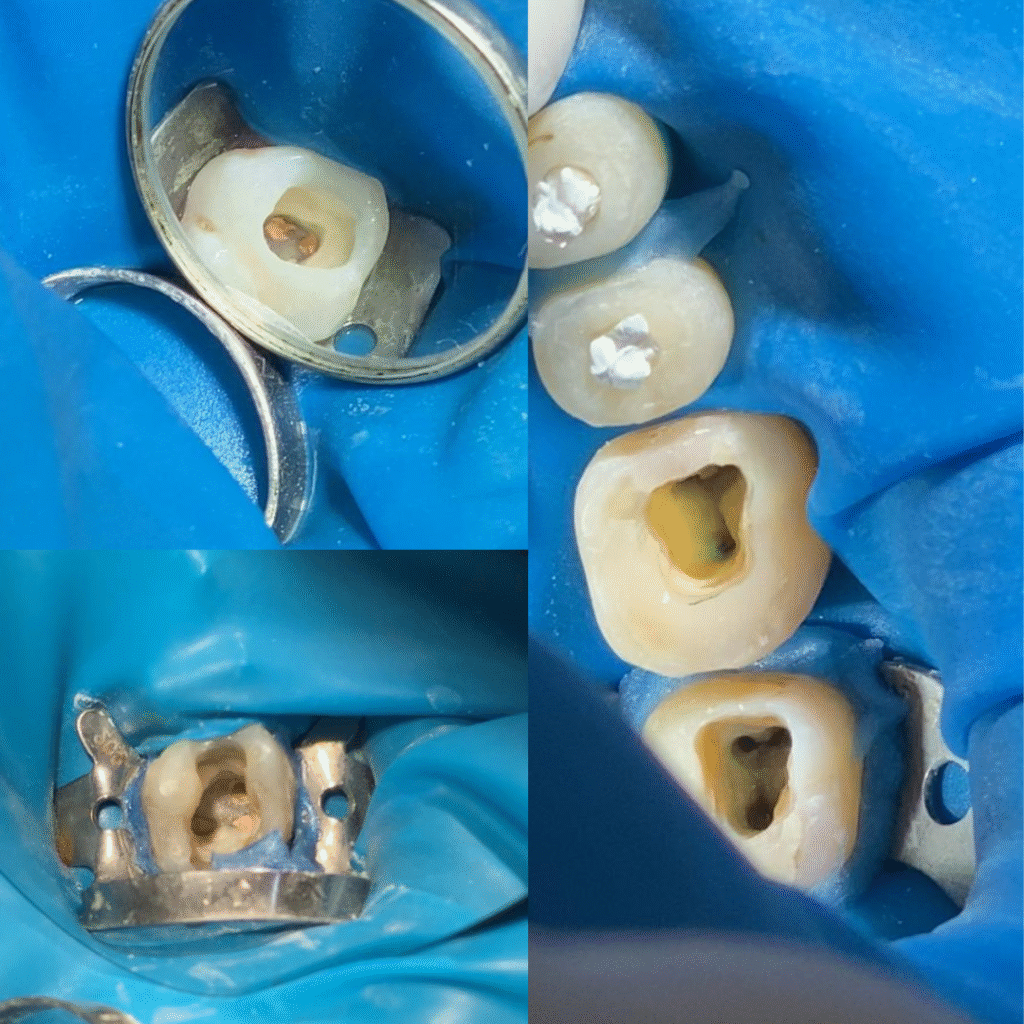

Isolamento do campo operatório, aumentando nosso campo de visão

Uso do raio x digital, permitindo um melhor diagnóstico pro seu caso

Diagnóstico preciso para confirmar a necessidade do canal

Tratamento completo no mesmo consultório: do canal à reconstrução final